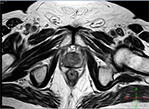

Пример МРТ простаты

МРТ простаты Мочевой пузырь расправлен, стенки его не изменены, содержимое однородное. Предстательная железа размерами 40,6х28,9х37,3 мм, обычной формы, с четкими, ровными контурами. Зональная анатомия железы сохранена. Междолевая борозда в срединном положении. Паренхима неоднородная за счет стромальной гиперплазии центральной зоны, наличия дополнительного образования в проекции периферической зоны справа на уровнях 18-21 ч.у.ц. Граница между капсулой железы и патологическим очагом стерта, прилежащая клетчатка бесструктурна. Ориентировочные размеры образования17х10,9мм. Слева, в проекции перифенической зоны определяется подобный очаг вытянутой формы на уровне 4-5 часов у.ц. протяженностью 12мм, толщиной7,2 мм, капсула железы интактна. Мр-сигнал в области основания правых семенных пузырьков низкий на Т2-ВИ. Ректопростатические углы не облитерированы. Нейроваскулярные пучки дифференцируются с обеих сторон. Простатическая часть уретры в срединном положении. Крупные сосуды таза не измене

Предстательная железа размерами 40,6х28,9х37,3 мм, обычной формы, с четкими, ровными контурами. Зональная анатомия железы сохранена. Междолевая борозда в срединном положении. Паренхима неоднородная за счет стромальной гиперплазии центральной зоны, наличия дополнительного образования в проекции периферической зоны справа на уровнях 18-21 ч.у.ц. Граница между капсулой железы и патологическим очагом стерта, прилежащая клетчатка бесструктурна.

Ориентировочные размеры образования17х10,9мм. Слева, в проекции перифенической зоны определяется подобный очаг вытянутой формы на уровне 4-5 часов у.ц. протяженностью 12мм, толщиной7,2 мм, капсула железы интактна.

Мр-сигнал в области основания правых семенных пузырьков низкий на Т2-ВИ.

Ректопростатические углы не облитерированы. Нейроваскулярные пучки дифференцируются с обеих сторон.

Простатическая часть уретры в срединном положении.

Крупные сосуды таза не изменены.

Увеличенных тазовых лимфатических узлов не определяется, паховые максимальным диаметром 8 мм справа.

Свободная жидкость не определяется.

ЗАКЛЮЧЕНИЕ по снимку МРТ простаты: МР-картина фокуса инвазивного Cr простаты справа с признаками инвазии основания семенных пузырьков справа без признаков видимой лимфаденопатии.